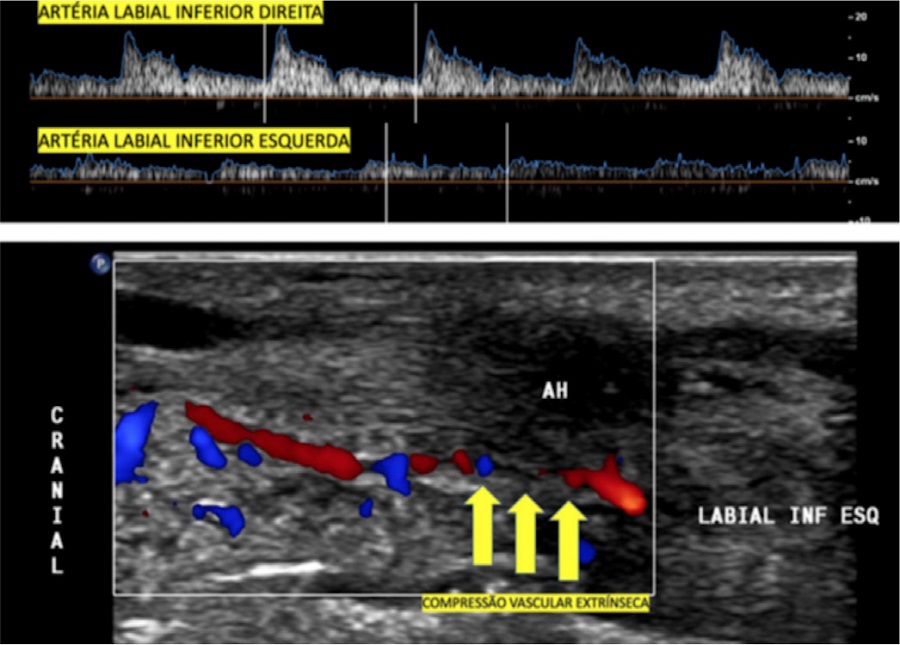

Paciente feminina, de 31 anos, procura dermatologista referindo edema importante nos lábios três horas após ter sido submetida a preenchimento labial com duas seringas de ácido hialurônico por caneta pressurizada a vácuo. Previamente ao procedimento, a paciente já havia se automedicado com 80mg de prednisona e 180mg de fexofenadina, por haver apresentado episódio de edema labial há quatro meses, após aplicação com agulha de 1 ml de ácido hialurônico. Na época, realizou teste alérgico aos anestésicos lidocaína e mepivacaína, ambos negativos. Ao exame físico, apresentava importante edema difuso, de aspecto endurecido nos lábios, com algumas equimoses, mas não apresentava palidez (Figura 1). Foi encaminhada para o exame de ultrassonografia de urgência, que demonstrou alterações da amplitude de fluxo e da resistência vascular entre as artérias labiais inferiores direita e esquerda, com redução dos picos de velocidade sistólica e queda da resistência vascular distalmente, o que sugere compressão extrínseca da artéria labial horizontal, porém sem sinais de oclusão (Figura 2). Além disso, observavam-se múltiplas áreas hipoecoicas de permeio, acometendo os lábios superior e inferior em toda a sua extensão, compatíveis com importante processo inflamatório focal após o uso do preenchedor. A paciente foi acompanhada clinicamente, foram prescritos prednisona 40mg ao dia e ciprofloxacino 500mg ao dia; devido à presença de fluxo, não necessitou de aplicação de hialuronidase. Em 24 horas, houve redução do edema, e a paciente permaneceu sem sinais de oclusão arterial.